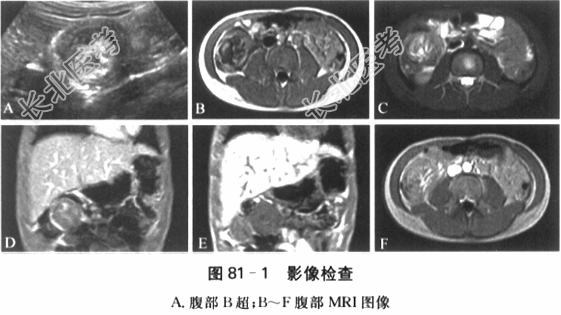

26.0mmol/L,GLU6.0mmol/L,BUN3.0mmol/L,Cr35μmol/L,UA114.0μmol/L,ALT20IU/L,AST20IU/L,AK73IU/L,γ-GT8IU/L,TB8.1μmol/L,DB0.0μmol/L,TP68.1g/L,ALB35.4g/L,GLB22.7g/L,A/G1.56,LDH458IU/L(313~618IU/L)。 (4)血清铁蛋白检测:9.7ng/ml(正常值24~160mmol/L)。 (5)DIC系列检测(2015-01-28):PT12.9s,APTT37.1s,TT15.1s,Fib3.33g/L,D-D0.1mg/L,INR0.99。 (6)X线胸片检查:两肺纹理粗,纵隔影未见增大。 (7)B超检查:右中腹见外径38mm类"同心圆"样包块;脐上局部肠管壁明显增厚达12mm,回声减低,彩色多普勒血流影像(CDFI)内部血流信号丰富,呈团块样,边界清,范围约56mm×33mm×38mm;阑尾未见增粗,回盲部见增大的淋巴结融合成团、范围约32mm×20mm×24mm,CDFI内部见条状血流信号。肠间隙见深达12mm游离无回声。结论:(慢性?)肠套叠;回盲部淋巴结增大融合成团;腹腔少量腹水。如图81-1A所示。 (8)腹增强MRI检查:各序列扫描见肝脏形态大小可,分叶清,信号未见明显异常;脾脏形态大小可,信号均匀;胰腺饱满,未见明显异常信号;双肾大小形态可,信号未见明显异常;右侧中腹部见占位性病变,范围4.44cm×4.63cm×9.14cm,边界欠清、边缘模糊,T1W等低信号、T2W高等混杂信号,增强后明显强化。结论:右侧中腹部占位性病变。如图81-1B~F所示。